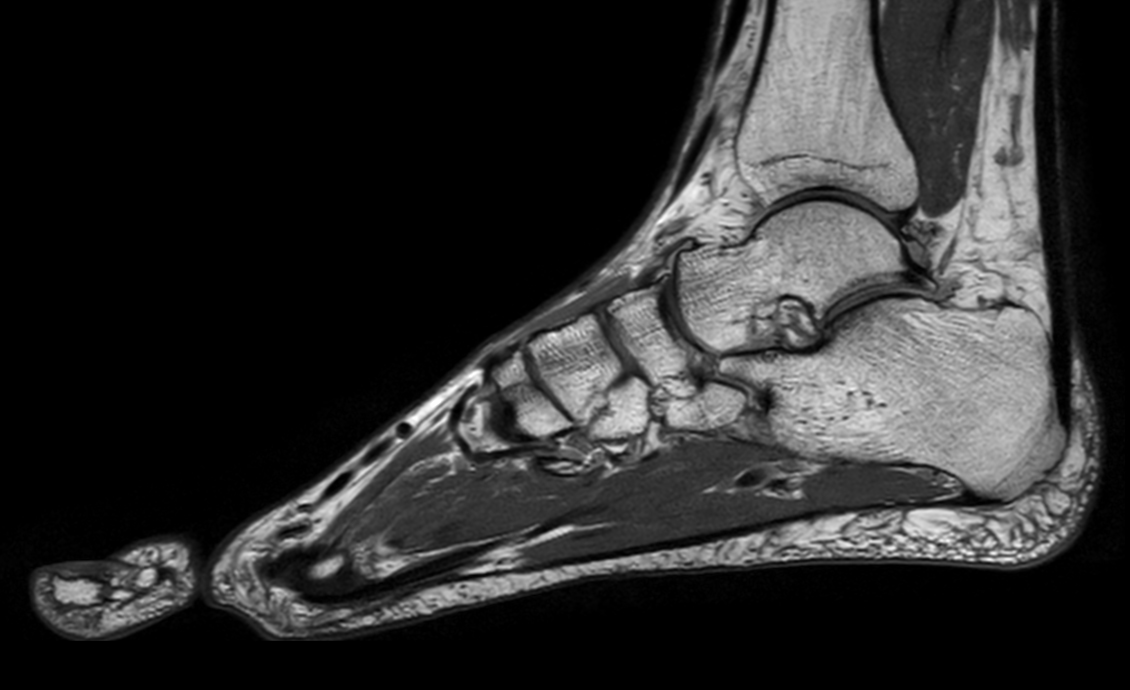

Ankle imaging with the dS 16ch FootAnkle coil

• Clinical Application